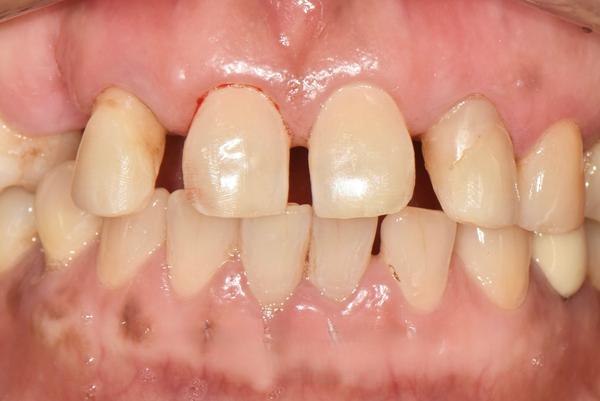

ハル歯科医院は、最先端のインプラント歯科治療に特化したクリニックです。代表のジョー・ハング院長は日本の神奈川歯科大学を卒業し、両国での歯科医師免許を保持。さらに、韓国で専門医資格を取得し、口腔外科など高度な手術経験も豊富です。すべての治療を院長自らが行う専任診療制を採用しており、流暢な日本語で対応可能。「デジタルインプラント」や「無削除ラミネート」などの最新のデジタル歯科治療を、日本の約半額で受けられます。仁川・金浦空港から乗り換えなしで行ける孔徳(コンドッ)駅すぐとアクセスも良好で、旅行者にも便利な立地となっています。